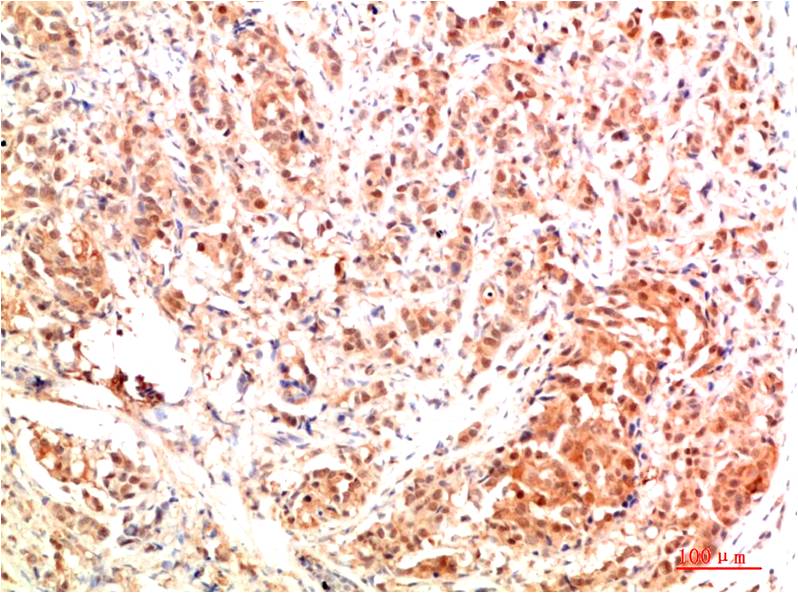

TTR Mouse Monoclonal Antibody(5G9)

Catalog NO.:BE3687

Applications :WB, IHC

Reactivity :H

| Recommended dilutions: | WB 1:1,000-2,000 IHC 1:100-200 |

| Specificity: | The TTR Mouse Monoclonal Antibody can detects endogenous TTR proteins. |